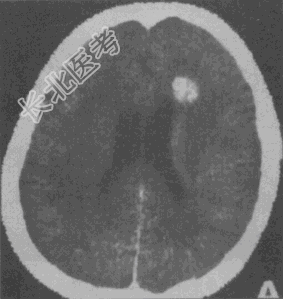

- 单项选择题女性,40岁。CT发现额叶异常密度灶, 无任何症状及体征。CT诊断(见图)最大可能是

A、正常钙化灶

B、脑膜瘤

C、少突胶质细胞瘤

D、海绵状血管瘤

E、脑出血